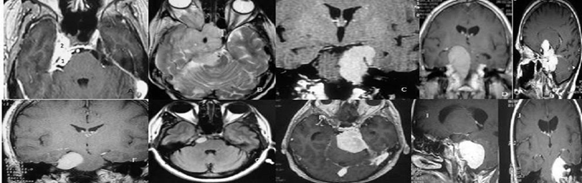

Se utilizan tres abordajes quirúrgicos principales en el manejo de los meningiomas petroclivales: abordaje pterional y sus variantes fronto-orbito-cigomático y pre- temporal, abordaje petroso y sus variantes petrosectomía posterior, anterior o total - “double petrosal approach”, y abordaje retrosigmoideo que se pueden combinar.1,28,29,38-48 Aunque los abordajes endoscópicos endonasales extendidos han evolucionado para controlar algunos meningiomas de la base del cráneo, especialmente los meningiomas de línea media del borde anterior del agujero magno, la posición del nervio abducente en el clivus, la consistencia endurecida de la mayoría de los meningiomas y, en menor medida, la extensión lateral de estos tumores en la fosa posterior, son factores limitantes para este procedimiento cuando se busca la resección máxima con baja o nula morbilidad.(41,29) El organigrama de decisión sobre cuál abordaje elegir puede consultarse en un estudio anterior.(28) Para racionalizar la elección del abordaje dividimos el clivus en tres tercios: tercio superior (del proceso clinoideo posterior al conducto trigeminal), tercio medio (del conducto trigeminal agujero yugular) y el tercio inferior, debajo del agujero yugular y correspondiente al borde anterior del agujero magno

Figura 1: Al decidir el abordaje del clivus podemos dividir el clivus superior (S) (entre el proceso clinoideo posterior y la entrada del nervio trigémino), el clivus medio (M) (entre la entrada del nervio trigémino y el agujero yugular) y el clivus inferior (I) (debajo del agujero yugular). 1. nervio trigémino, 2. complejo vestíbulo coclear con arteria cerebelosa anteroinferior (AICA) 3. nervio abducens, 4. arteria cerebelosa superior 5. arteria cerebelosa postero inferior (PICA), arteria basilar (BA) y arteria vertebral (VA).

Otro factor que se tiene en cuenta es la existencia de una extensión en la fosa media que puede estar dentro del seno cavernoso, en la pared lateral del seno cavernoso, o en ambos.

Figura 2: El estudio de la posición del tumor en el clivus, y la extensión o no de éste en la fosa media, sirve para decidir el abordaje. Para los tumores con un componente solo en el clivus superior, se utilizó un abordaje pterional pretemporal, abriendo la muesca de la carpa y eliminando el tumor del clivus superior que estaba comprimiendo el nervio trigémino y causando neuropatía (A). Para este meningioma esfenopetroclvial anaplásico se utilizó el abordaje craneo-órbito-cigomático con petrosectomía anterior con extirpación tumoral. El paciente se sometió previamente a cirugía con ojo congelado (frozen eye) (B). El abordaje petroso posterior (pre-sigmoide supra / infratentorial) se usa para meningiomas petroclivales con extensión tumoral en la fosa media (C, D, E). Para los meningiomas petroclivales localizados completamente en la fosa posterior, el abordaje retrosigmoideo es suficiente independientemente del tamaño del tumor (F, G, H, I, J).